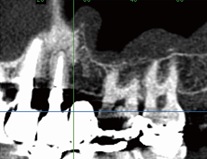

2.金属の影響を除去

口の中は体の他の部分とは違い、歯の詰め物や被せものとして金属があります。金属はX線を通しにくいため、その影響でこれまでのCTでは周りの骨の状態が把握できないことがありました。

当院の歯科用CTは金属の影響を除去するプログラムを搭載していますので、他のCTでは金属の影で映らない部分の骨でも診断することができます。

これまでのCT

金属の周りが黒く

なり映っていません。

|

当院の歯科用CT

金属の周りでも骨の

状態を診断できます。